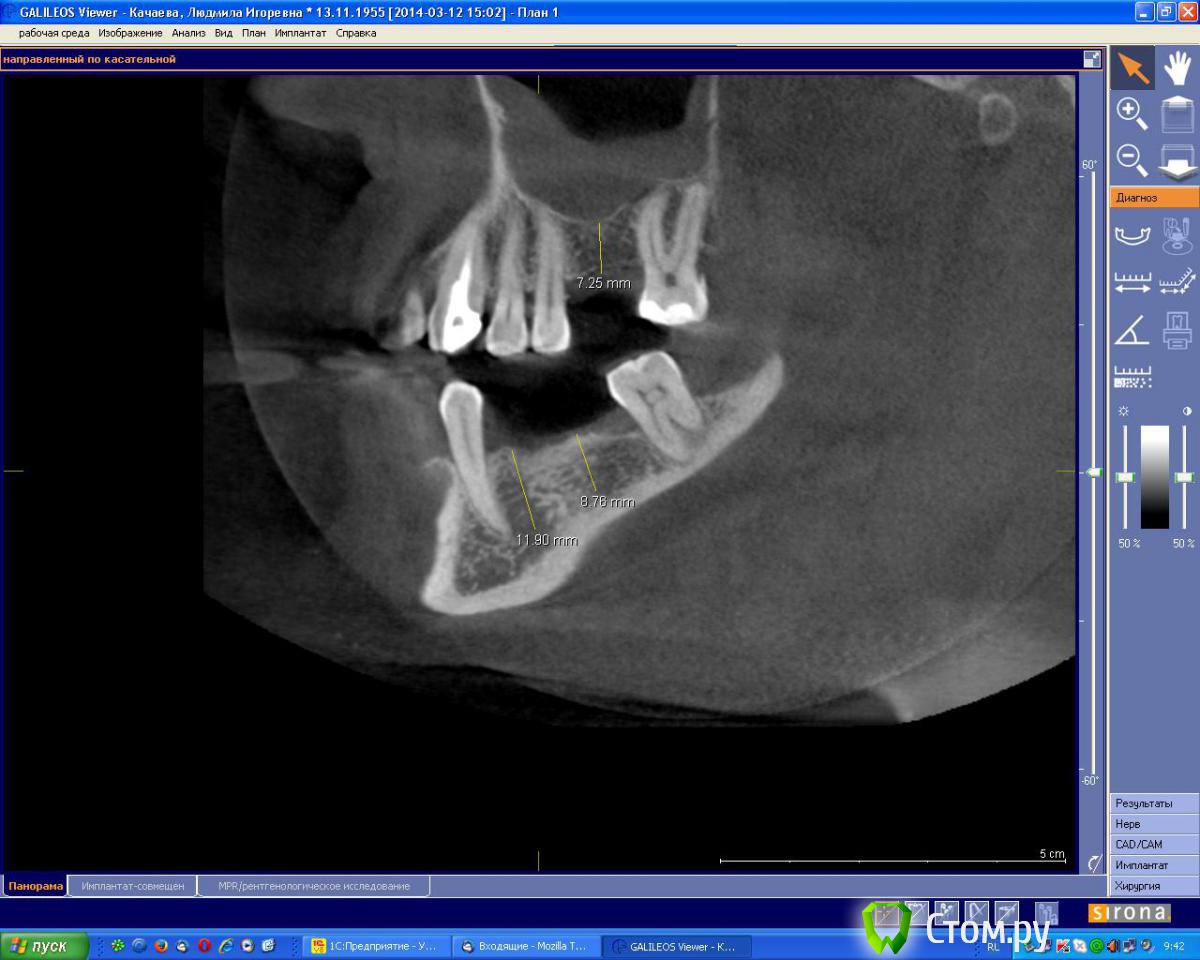

an_ver Опубликовано 7 августа, 2014 Поделиться Опубликовано 7 августа, 2014 Планируется установка 2 имплантов в обл.35,37 по высоте проходит,по толщине нет.Предпочтительный метод в данной ситуации? Ссылка на комментарий

Аслан Опубликовано 7 августа, 2014 Поделиться Опубликовано 7 августа, 2014 (изменено) Вот тут бы без сомнений просто поставил чуть поглубже и вестибулярно досыпал.Хотя можно и заморочиться и перевернуть блок, как показывал Эдуард. Изменено 7 августа, 2014 пользователем Аслан 4 Ссылка на комментарий

Тимур86 Опубликовано 7 августа, 2014 Поделиться Опубликовано 7 августа, 2014 Поддержу!просто поставить поглубже,высота там хорошая Ссылка на комментарий